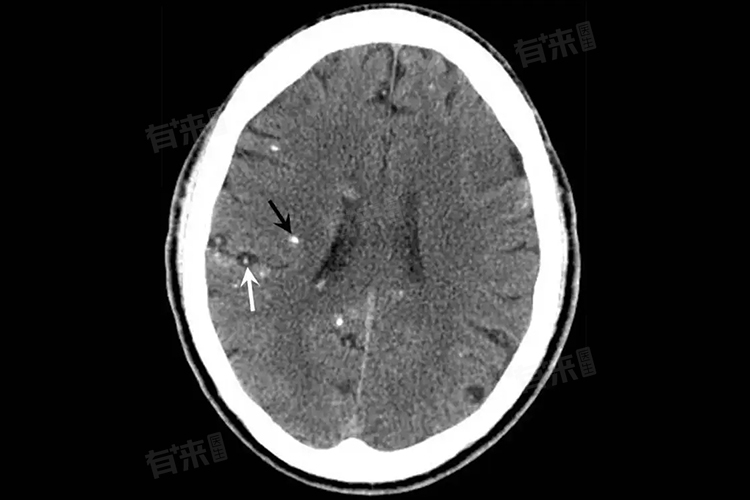

脑内寄生虫的种类较多,常见的有脑囊虫、脑包虫、弓形虫等。这些寄生虫进入人体的途径多样,主要通过食用被寄生虫卵污染的食物或水源,如未洗净的蔬菜、生水等,也可因接触感染动物(如猫、狗等)而感染。诊断脑内寄生虫主要依靠详细的病史询问、体格检查、血液寄生虫抗体检测、脑脊液检查以及影像学检查(如头颅CT、MRI)等。